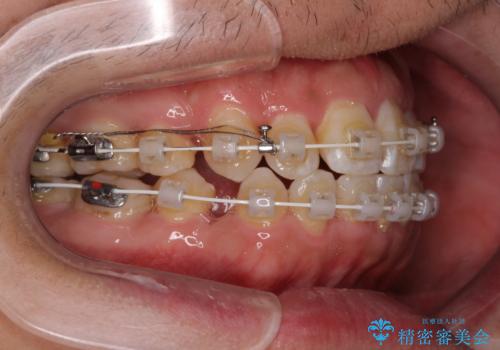

前歯のデコボコを抜歯矯正で改善した症例|目立ちにくい審美装置を使用

- 「歯並び全体のデコボコをきれいに整えたい」とのご希望で、20代男性の患者様が来院されました。

特に前歯部の叢生(歯の重なり)が強く、見た目だけでなく歯磨きのしにくさも気にされていました。

診査の結果、上下前歯に強い叢生が認められ、歯をきれいに並べるためのスペースが明らかに不足していました。

無理に歯を並べると、前歯が前方に突出するため、抜歯によるスペース確保が必要と判断しました。

上下左右の小臼歯を抜歯し、歯列を整えるためのスペースを確保

左下は第二小臼歯に根管治療歴があったため、左下のみ第二小臼歯を抜歯しアンカースクリューを併用

それ以外の部位は第一小臼歯を抜歯

矯正中の見た目を気にされていたため、プラスチックブラケット+コーティングワイヤーを使用した、目立ちにくい審美矯正装置を選択しました。